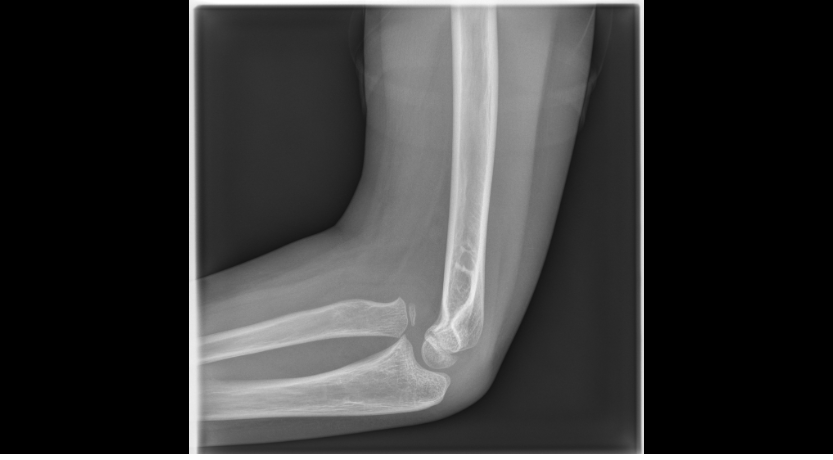

Short Cases for FRCR 2B (1-5) ....6th packet on the way